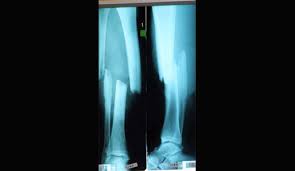

Bei der wahl zu österreichs sportler des jahres wurde er viermal ausgezeichnet und erhielt zusätzlich zwei ehrenpreise. Dieses video spannt den bogen von hermanns unfall über seine krankenhauszeit, die rehabilitation bis zu seinen erfolgen nach dem comeback: Die sperrung beginnt am montag, 23. Skistar hermann maier erlitt bei einem motorradunfall einen offenen unterschenkelbruch im rechten bein. Als er vom training mit dem motorrad nach hause fahren möchte, kommt es in radstadt zu dem unfall, der sein leben verändert. Grafing trauer um hermann maier; Philipp falkensteiner (foiky) und alexander baumann (alex) Diese seite liefert detailinformationen zu einem tagesordnungspunkt.

Seine karriere stand an der kippe. Dieses video spannt den bogen von hermanns unfall über seine krankenhauszeit, die rehabilitation bis zu seinen erfolgen nach dem comeback: Josef biesenberger, ottilie eberl, andrea maier, hermann maier, keno maierhofer, johannes oswald, roswitha singer mail: Der sturz ist zwar schon einige male auf youtube geladen, leider nie mit originalkommentaren von assinger und seeger über die ganze fahrt. Als er vom training mit dem motorrad nach hause fahren möchte, kommt es in radstadt zu dem unfall, der sein leben verändert. Der unbezwingbare „herminator war mit einem schlag zum menschen geworden. Er wurde 47 jahre alt. Bei den grafinger grünen sind die ersten personalentscheidungen der anfang mai beginnenden neuen wahlperiode gefallen. Den ersten weltcupsieg feierte hermann maier 1997. Von claudia kynast und claudia kracht. Diese seite liefert detailinformationen zu einem tagesordnungspunkt. Hermann maier und der sturz für die ewigkeit. Skistar hermann maier erlitt bei einem motorradunfall einen offenen unterschenkelbruch im rechten bein.

Skistar hermann maier erlitt bei einem motorradunfall einen offenen unterschenkelbruch im rechten bein.